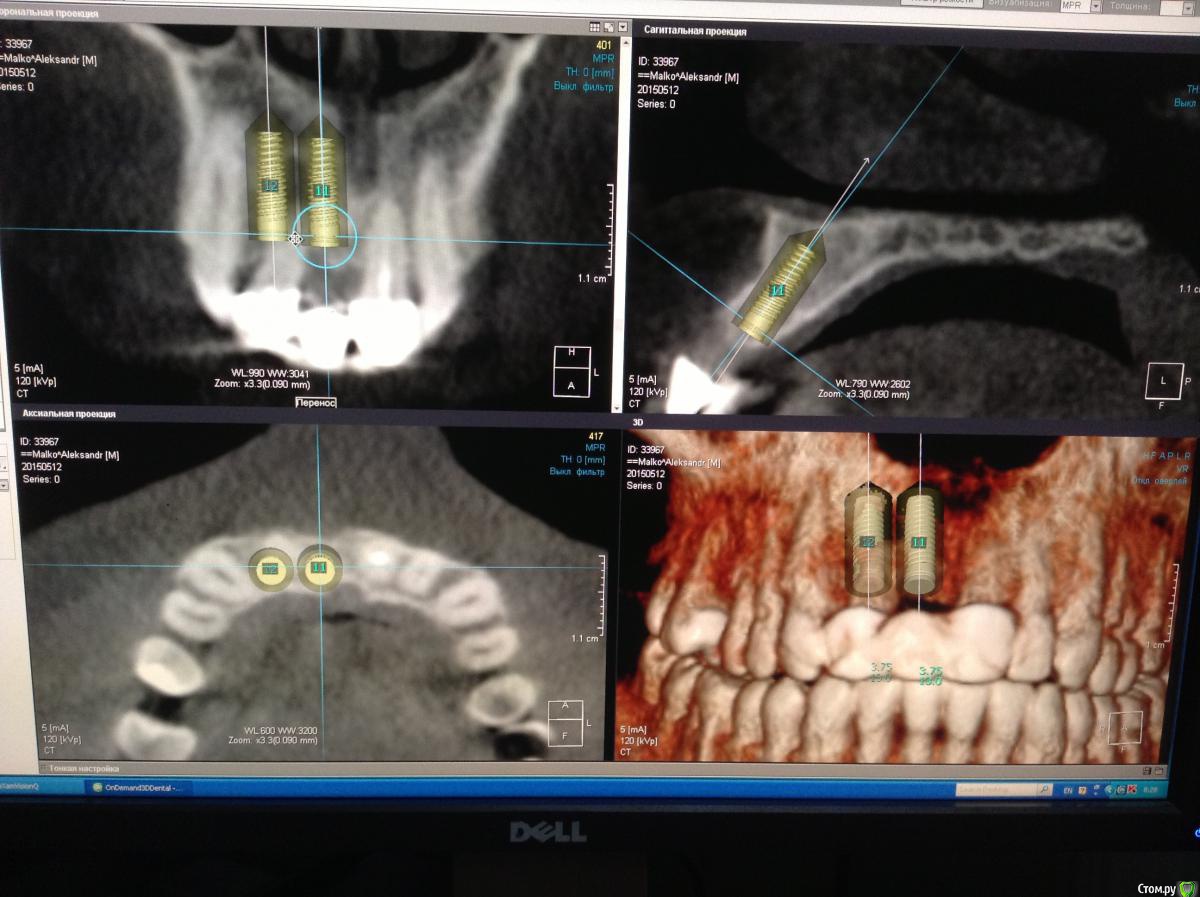

Pro100Andre Опубликовано 10 июля, 2015 Автор Поделиться Опубликовано 10 июля, 2015 Вот так получилось 12 терапевты не решились перелечивать Ссылка на комментарий